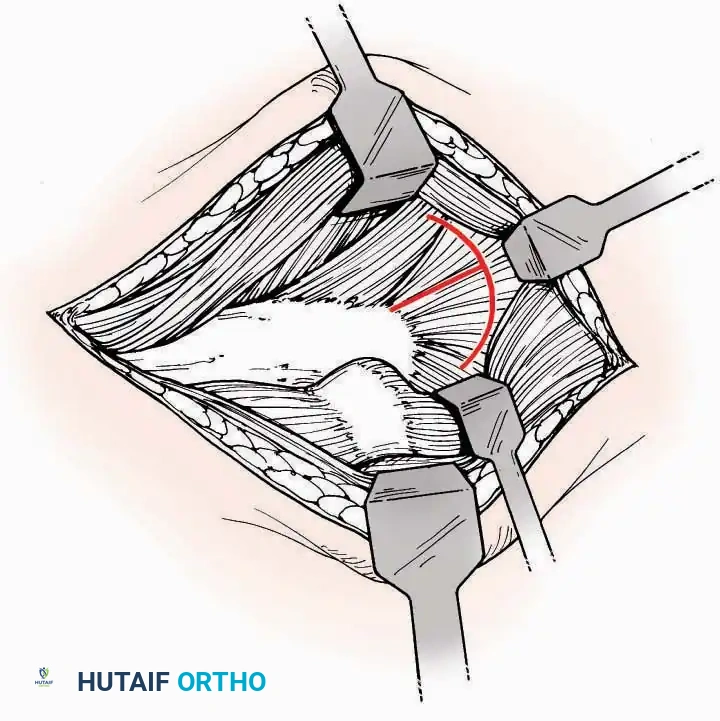

Anterolateral Approach

The anterolateral approach is widely considered the "universal incision" for the foot and ankle. It provides unparalleled access to the ankle joint, the talus, and the majority of the tarsal articulations, while safely avoiding the major anterior neurovascular bundle. The only tarsal joints inaccessible via this route are the naviculocuneiform joints (specifically the medial and intermediate).

Indications: Total talectomy, triple arthrodesis, ankle arthrodesis, and open reduction of complex talar neck fractures.

Surgical Technique:

* Incision: Begin over the anterolateral aspect of the leg, medial to the fibula and 5 cm proximal to the ankle joint line. Carry it distally over the joint, crossing the anterolateral aspect of the talar body and the calcaneocuboid joint, terminating at the base of the fourth metatarsal.

* Superficial Dissection: Incise the superficial fascia and the superior and inferior extensor retinacula down to the periosteum of the tibia and the ankle joint capsule.

* Vascular Ligation: This trajectory usually requires the identification and ligation of the anterolateral malleolar and lateral tarsal arteries.

* Nerve Protection: Retract the skin edges carefully. Identify and protect the intermediate dorsal cutaneous branches of the superficial peroneal nerve (SPN), which frequently cross the distal aspect of this incision.

* Muscle Management: Identify the origin of the extensor digitorum brevis (EDB) muscle on the lateral calcaneus. Divide it in the direction of its fibers, or detach its origin entirely and reflect it distally to expose the subtalar and calcaneocuboid joints.

* Deep Exposure: Retract the extensor digitorum longus (EDL) tendons, the dorsalis pedis artery, and the deep peroneal nerve (DPN) medially. Incise the anterior ankle capsule to expose the tibiotalar joint.

* Tarsal Exposure: Expose the talonavicular joint by dissecting deep to the extensor tendons and incising its capsule transversely. Continue laterally through the capsule of the calcaneocuboid joint. By excising the fat pad within the sinus tarsi (lateral and inferior to the talar neck), the posterior facet of the subtalar joint is brought into direct view.